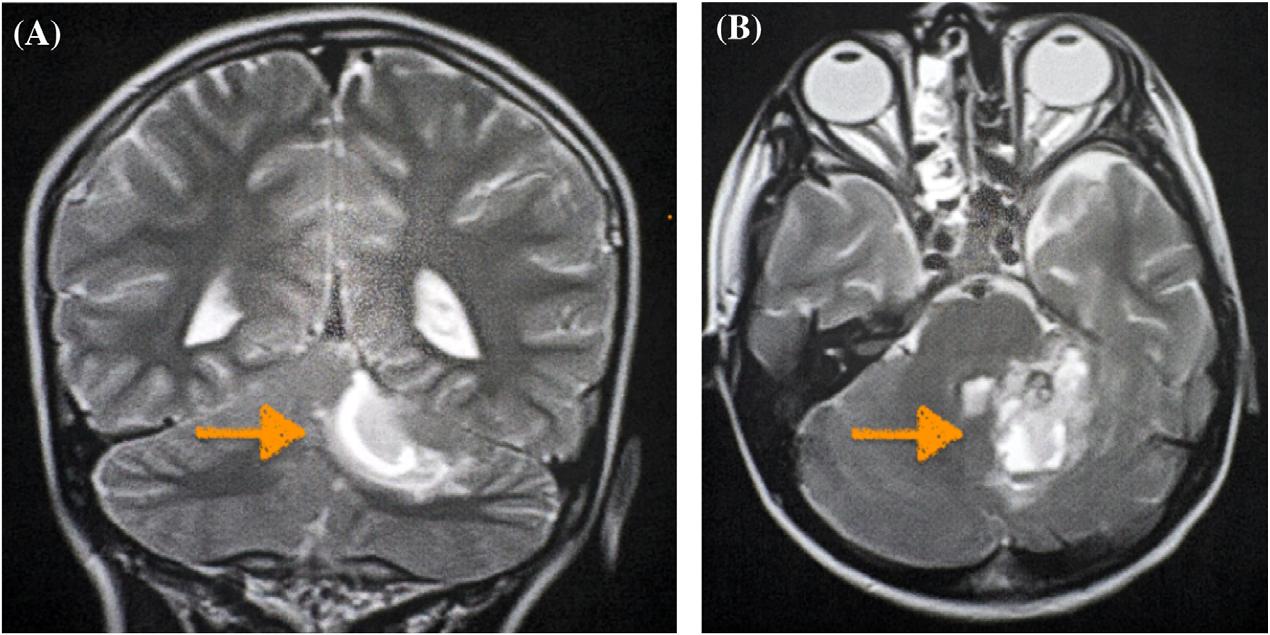

345 A Pediatric Case Report of Acute Torticollis Secondary to Atraumatic Cerebellar Hemorrhage

JA Enabore, R Vezzetti, G Hill